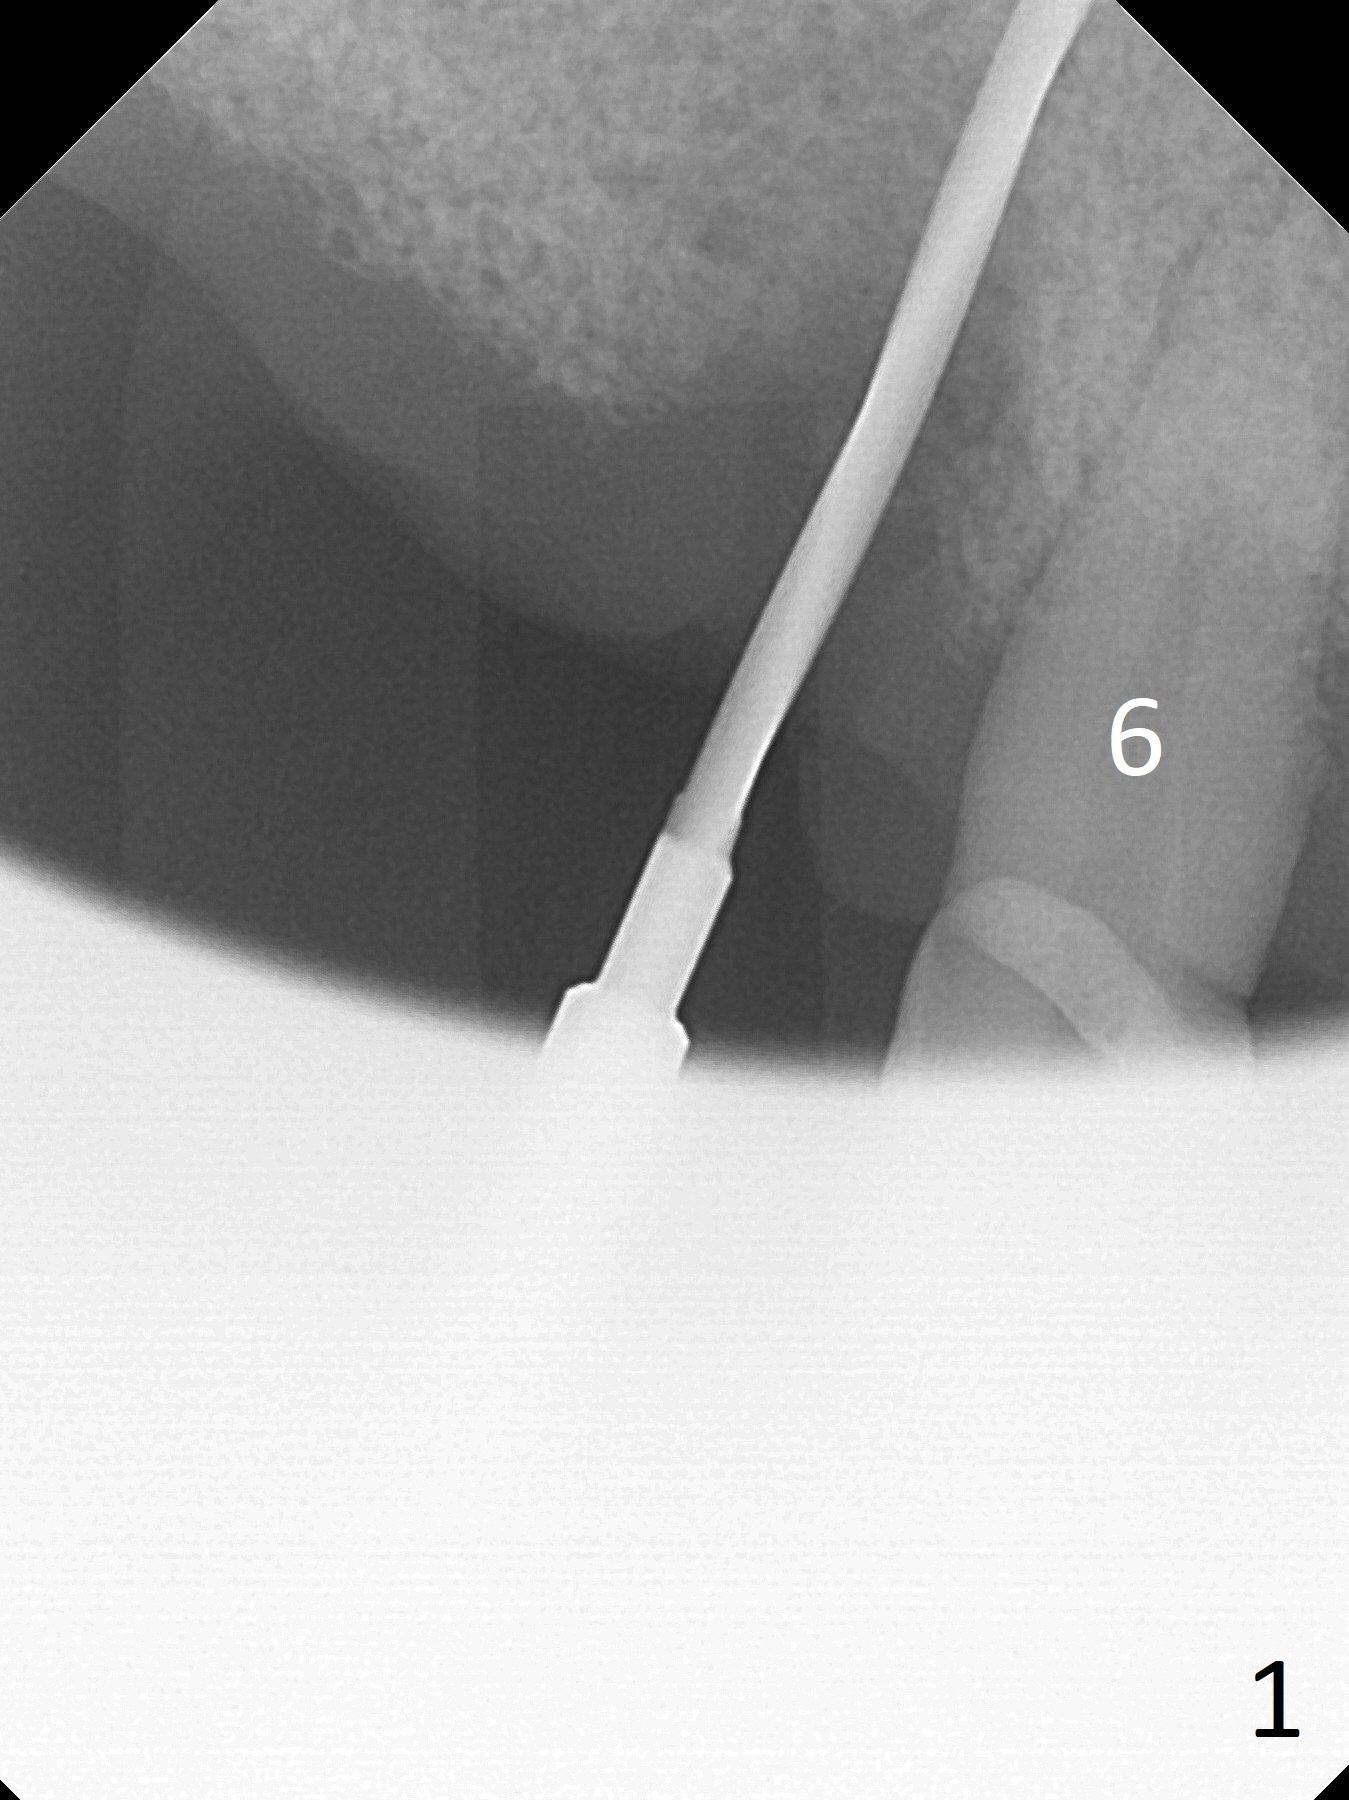

Extraction of the tooth #5 with mobility III reveals no buccal plate and low palatal plate.  Osteotomy starts as palatal as possible (Fig.1).  The bone density is low.  After use of 2.7 mm drill (Fig.2), a 3 mm drill can be inserted into the osteotomy without resistance.  A 4x16 mm implant is placed with insertion torque <30 Ncm.  When an abutment is placed, the implant is found to have been placed distal.   The implant is untorqued for change in trajectory.  When a 4.5x7(5) mm abutment is placed, the abutment turns with the underlying implant (Fig.3).  The former is kept to be turned with a hand driver until the latter is unable to turn.  Following placement of allograft (Fi.g3,4 *), a mini-provisional is fabricated to retain the bone graft and at the same time not to be interfered with when a flipper is in and out.  The bone graft in the former socket gap appears to have integrated into the native one 4.5 months postop (Fig.5).